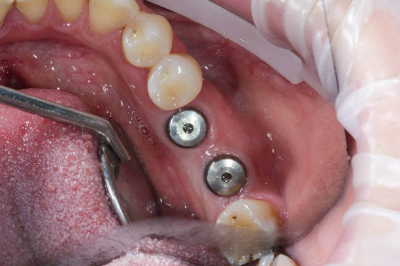

환자분(김ㅇ진님)은 #34 부위에 임플란트 수술을 받으셨습니다. 수술은 약 30분 만에 순조롭게 마쳤습니다.